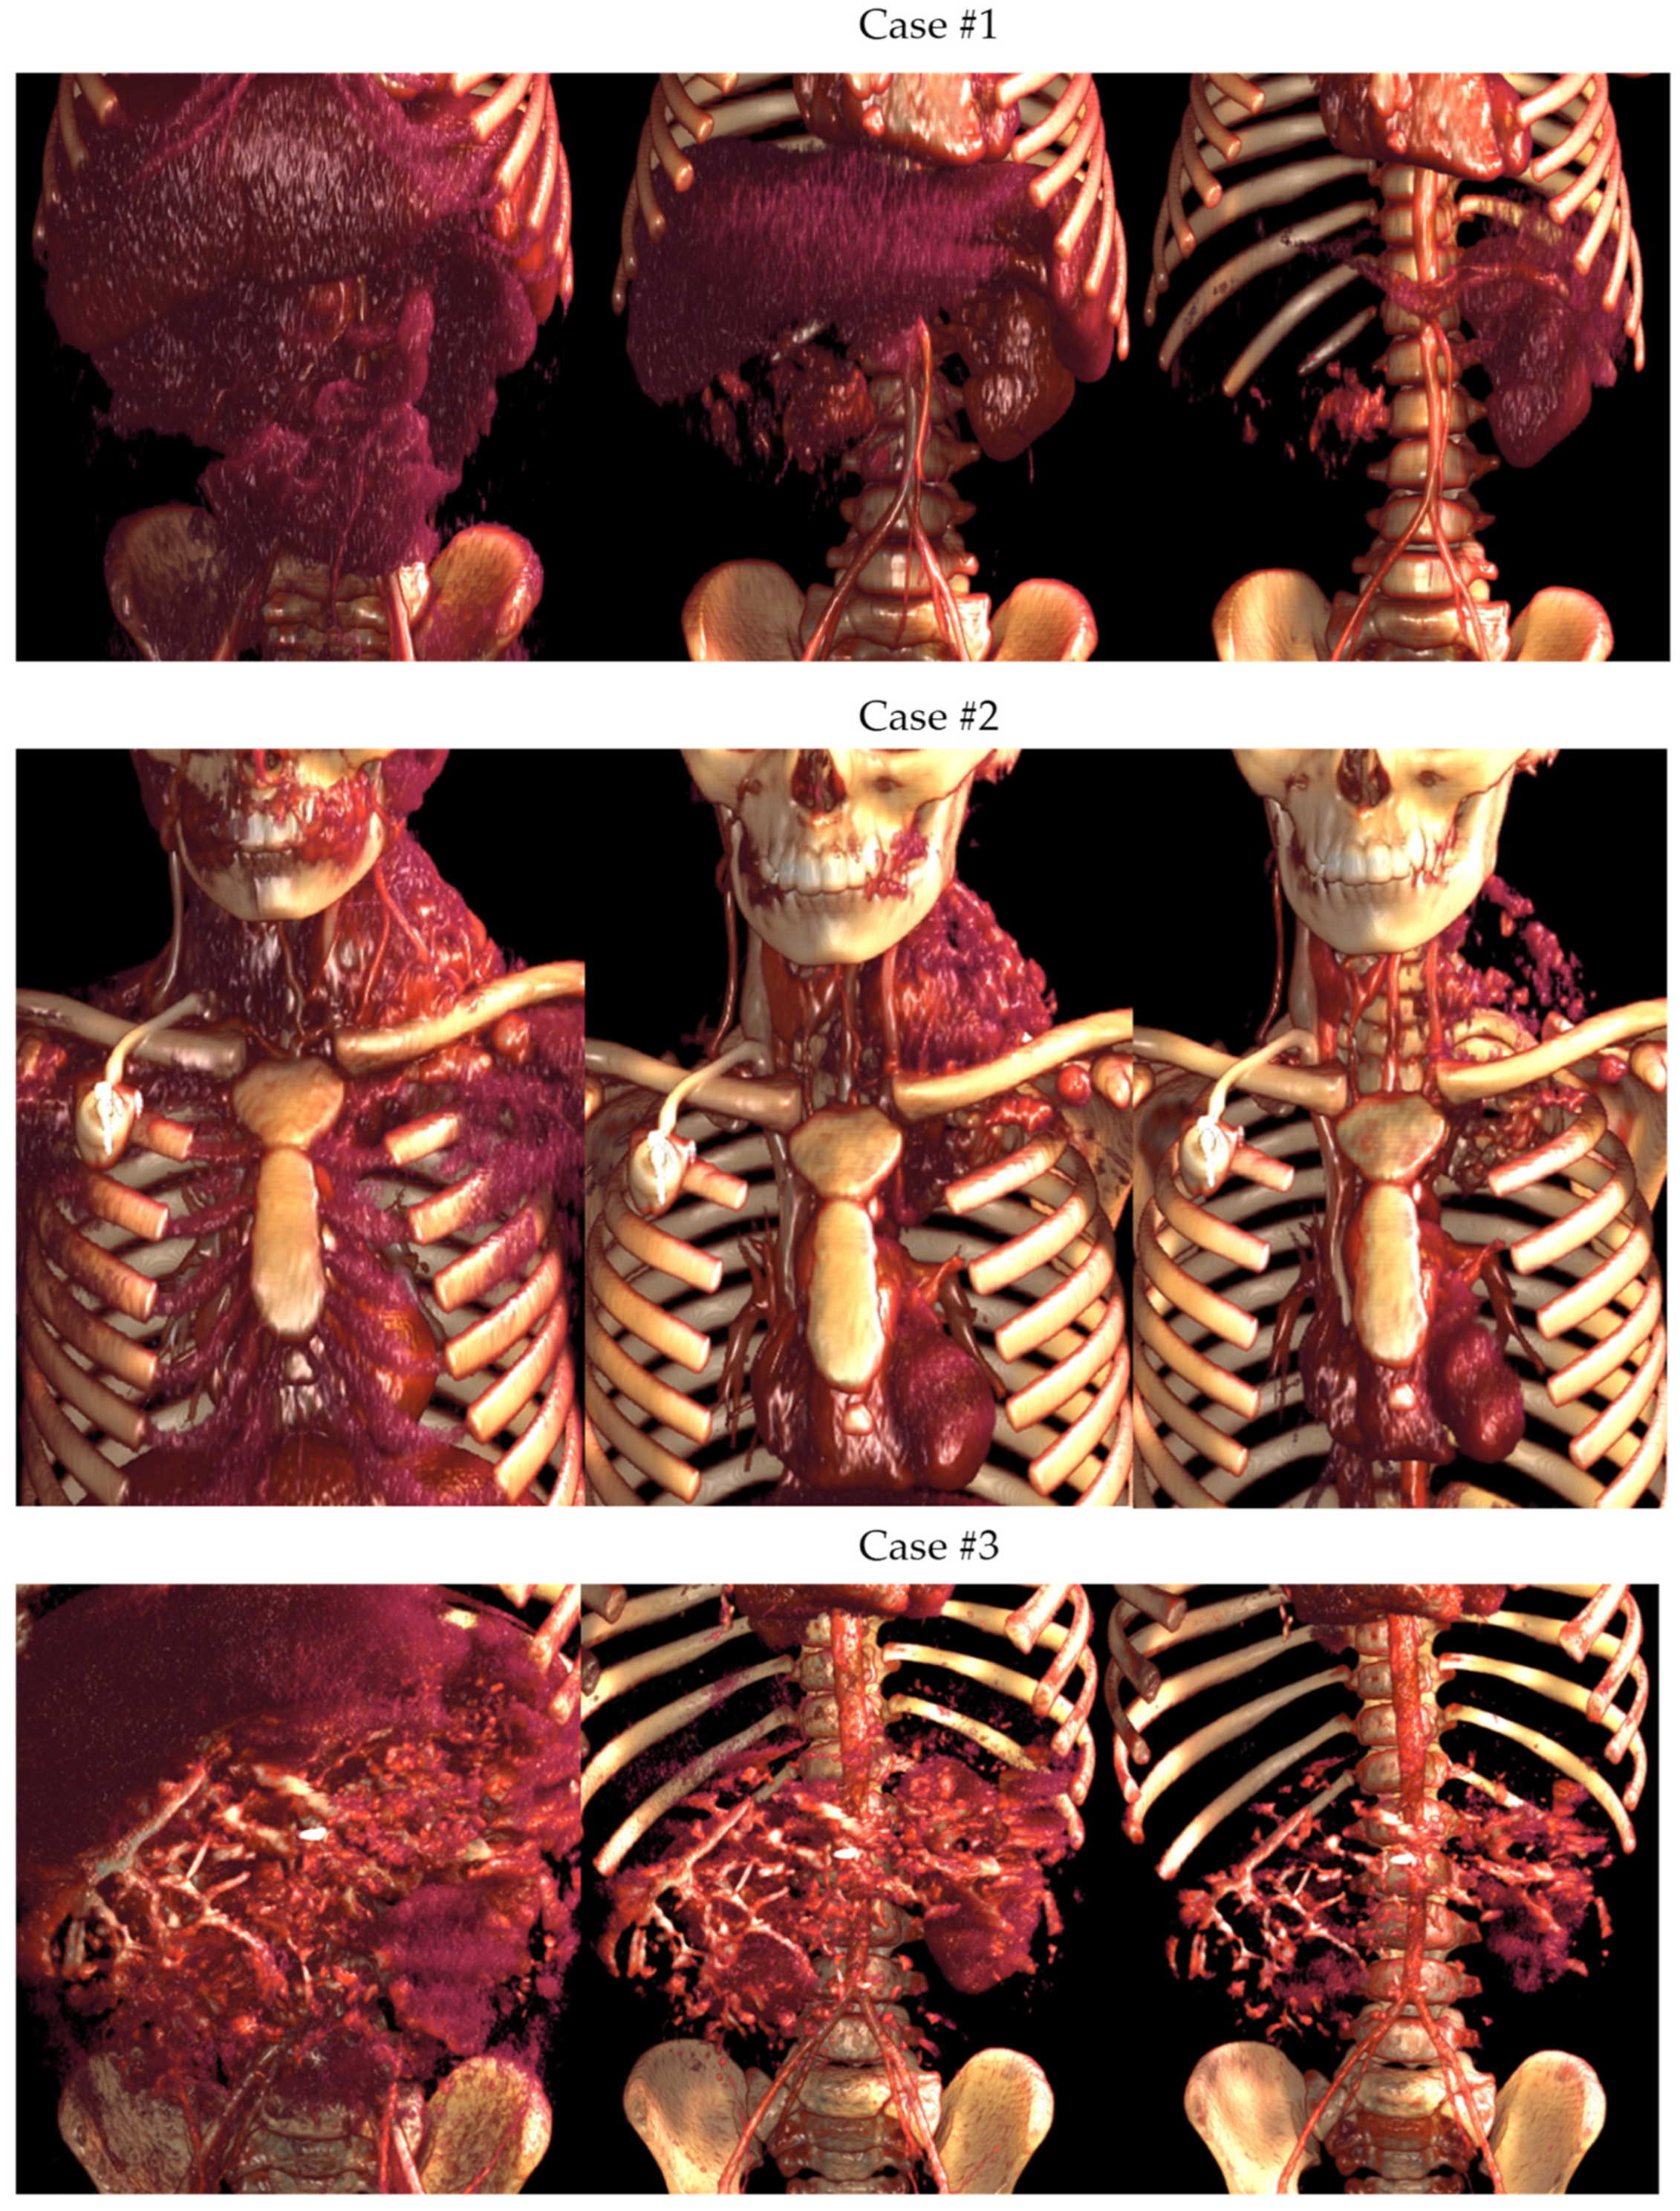

3.1.2. Volume Rendering and Cinematic Rendering